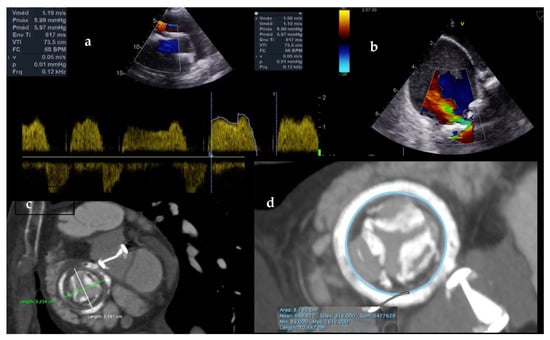

6.1. Procedure